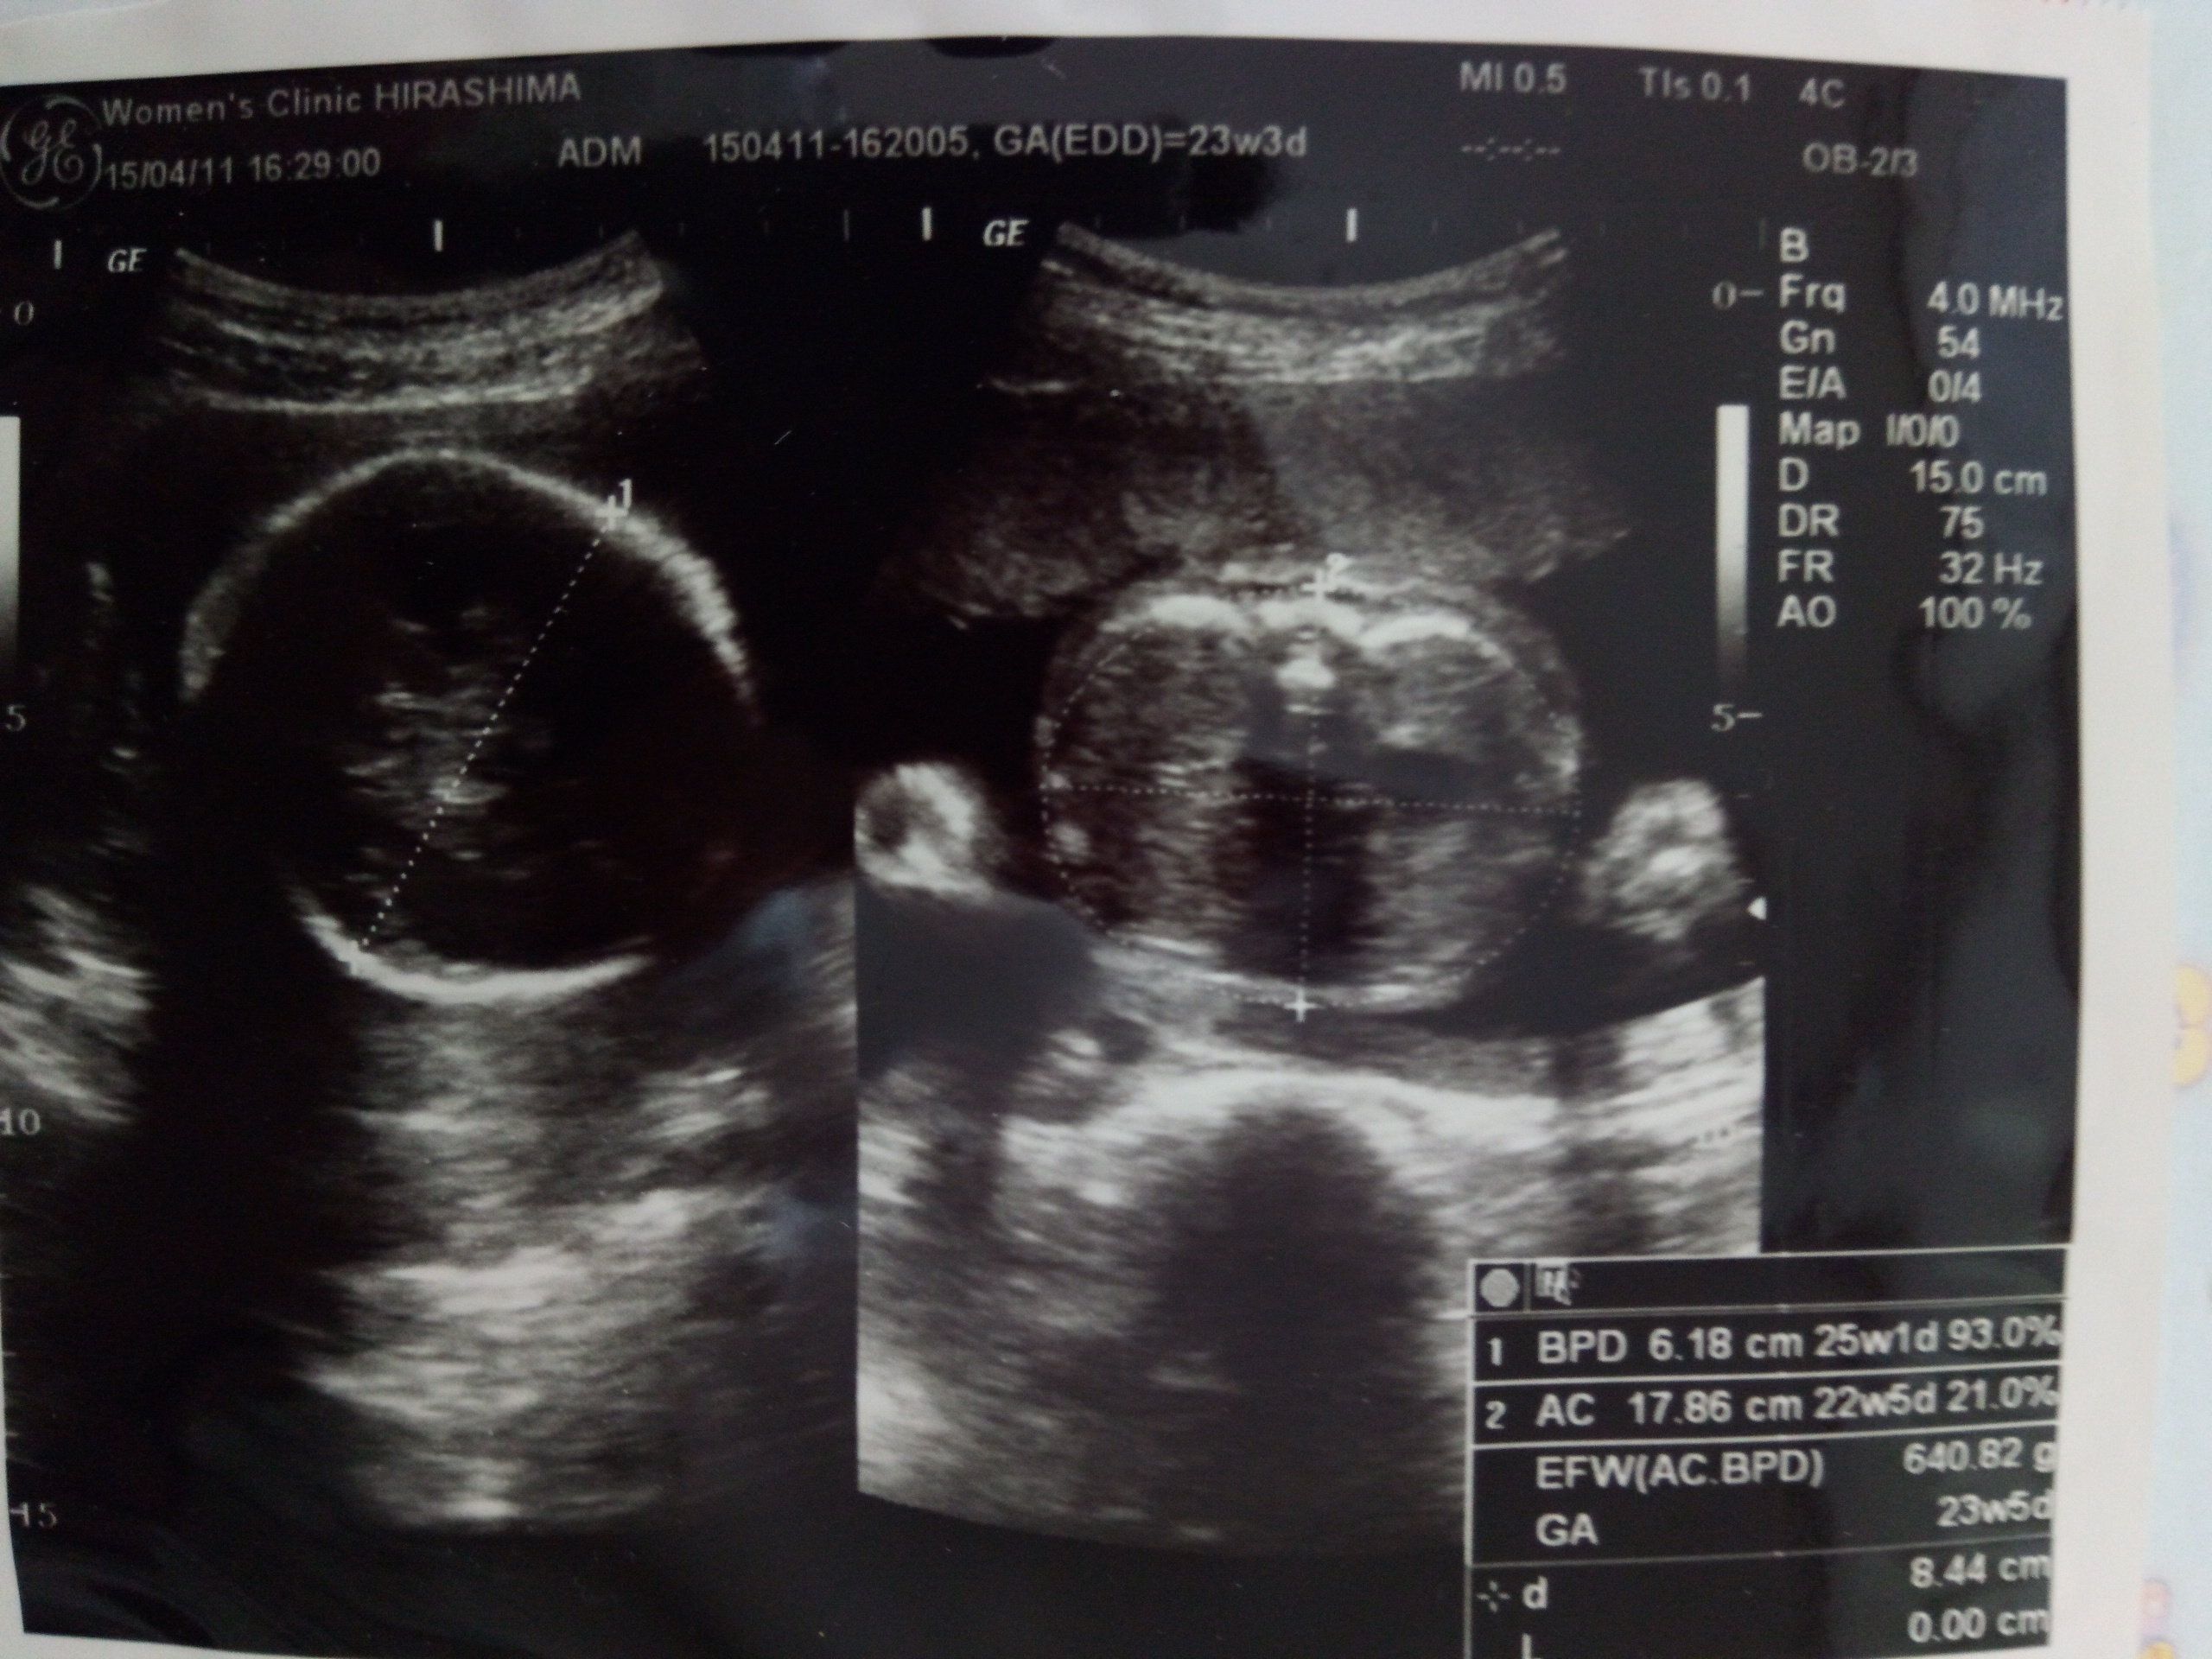

妊娠23週のエコー写真 赤ちゃんの推定体重640g

この日、体重増加の注意が入ってしまいました。(+5kgでした。)けれど、安静指示は解けず、食事量も増えてはおらず、思わず「どうやって体重管理しればいいんですか」と、突っ込んでしまいました。白米を減らすなど、食事の工夫をするようアドバイスされました。